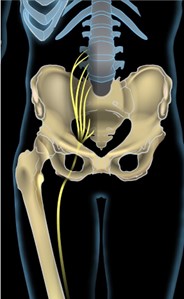

⚪︎人体最大の神経「坐骨神経」の走行ルート

坐骨神経は、人体で最も太く、最も長い末梢神経です。この坐骨神経のどこか一箇所でも神経が圧迫されると、その神経の支配領域であるお尻から足先にかけて、痛みやしびれが発生します。